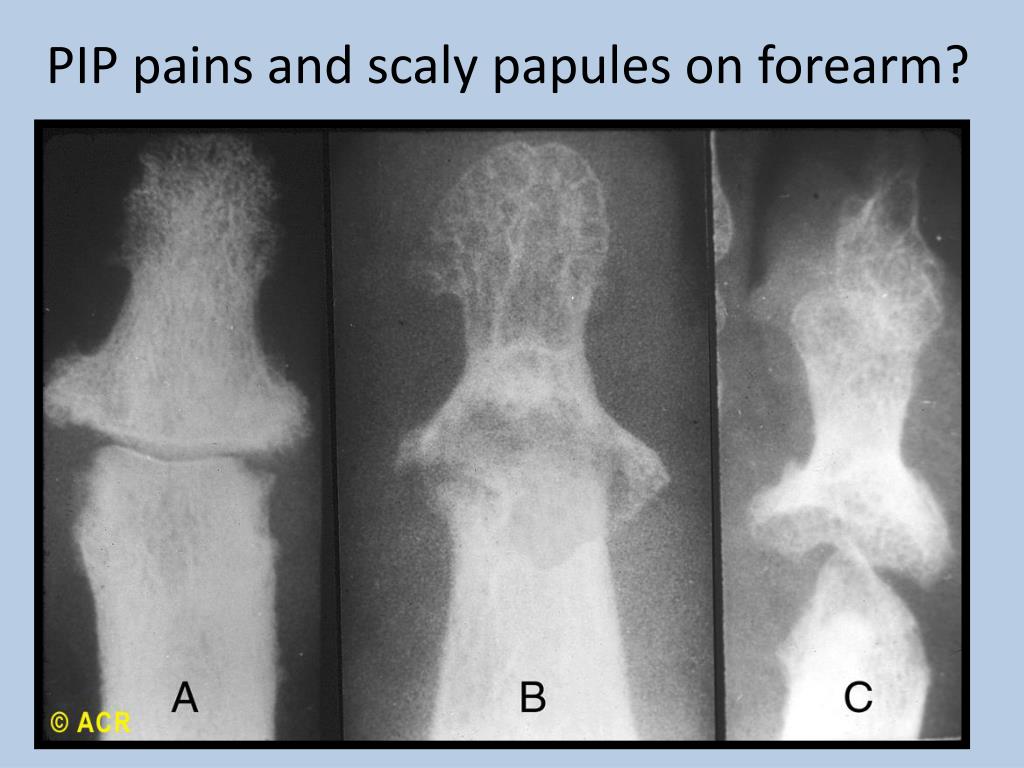

Ревматоидный артрит стопы: рентгеновские снимки и стадии заболевания

Раздел: Визуальный дайджест